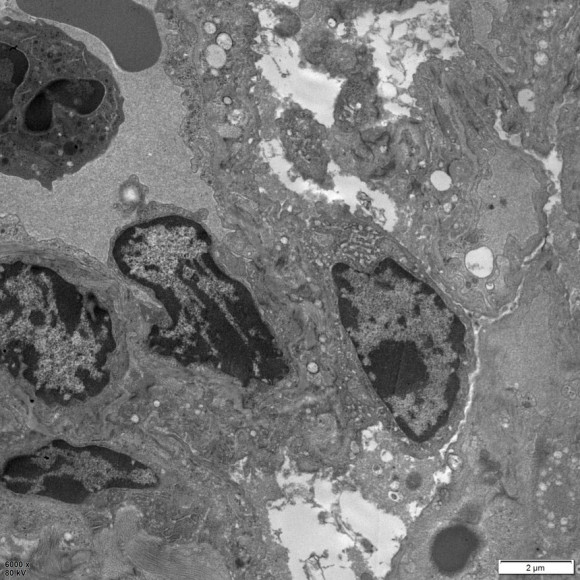

正常 COPD模型 超微结构变化: 正常组:未见明显肺泡腔,实性变,细胞连接紧密,未见明显绒毛脱落和坏死;细胞核不规则,线粒体、内质网均 清晰可见,少量线粒体空泡变;板层小体未见。

模型组: 肺泡间隔增宽,细胞连接松懈;毛细血管内充血;上皮细胞有绒毛的脱落和坏死;细胞核均出现不同程度的核形 不规则,线粒体数量变化不明显,可见线粒体肿胀,部分线粒体嵴消失,呈空泡状;可见溶酶体;可见板层小体排空。